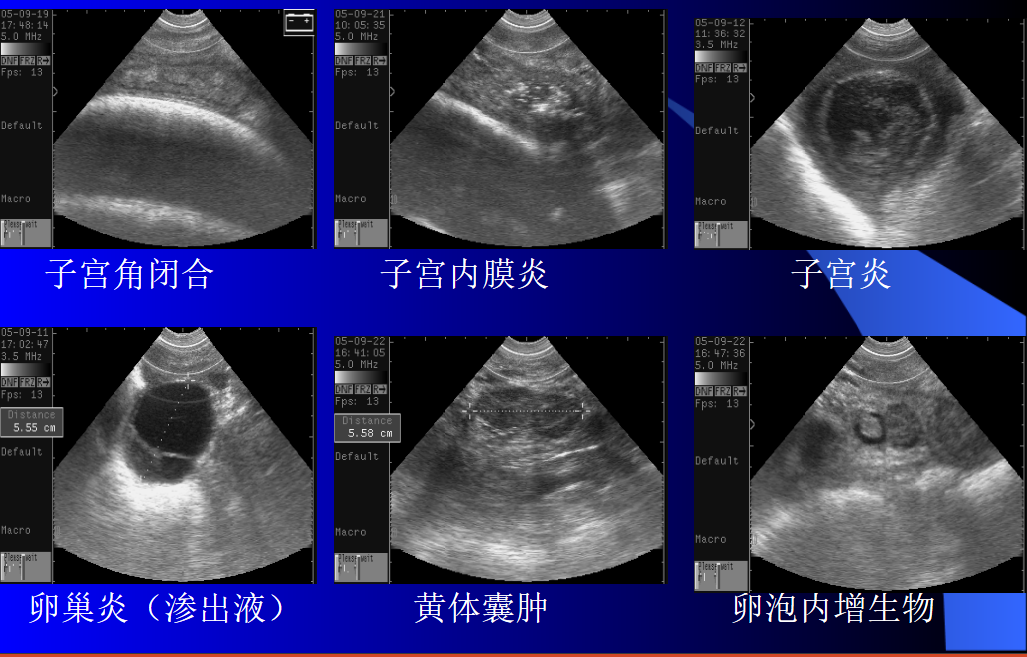

3、另外还要区分胎囊、卵泡和膀胱,由于三者位置相近,并都呈无回声暗区,易造成判断失误;

4、探查部位应选择靠近生殖器官的部位,避免因胎囊沉于子宫角底部而造成失误。